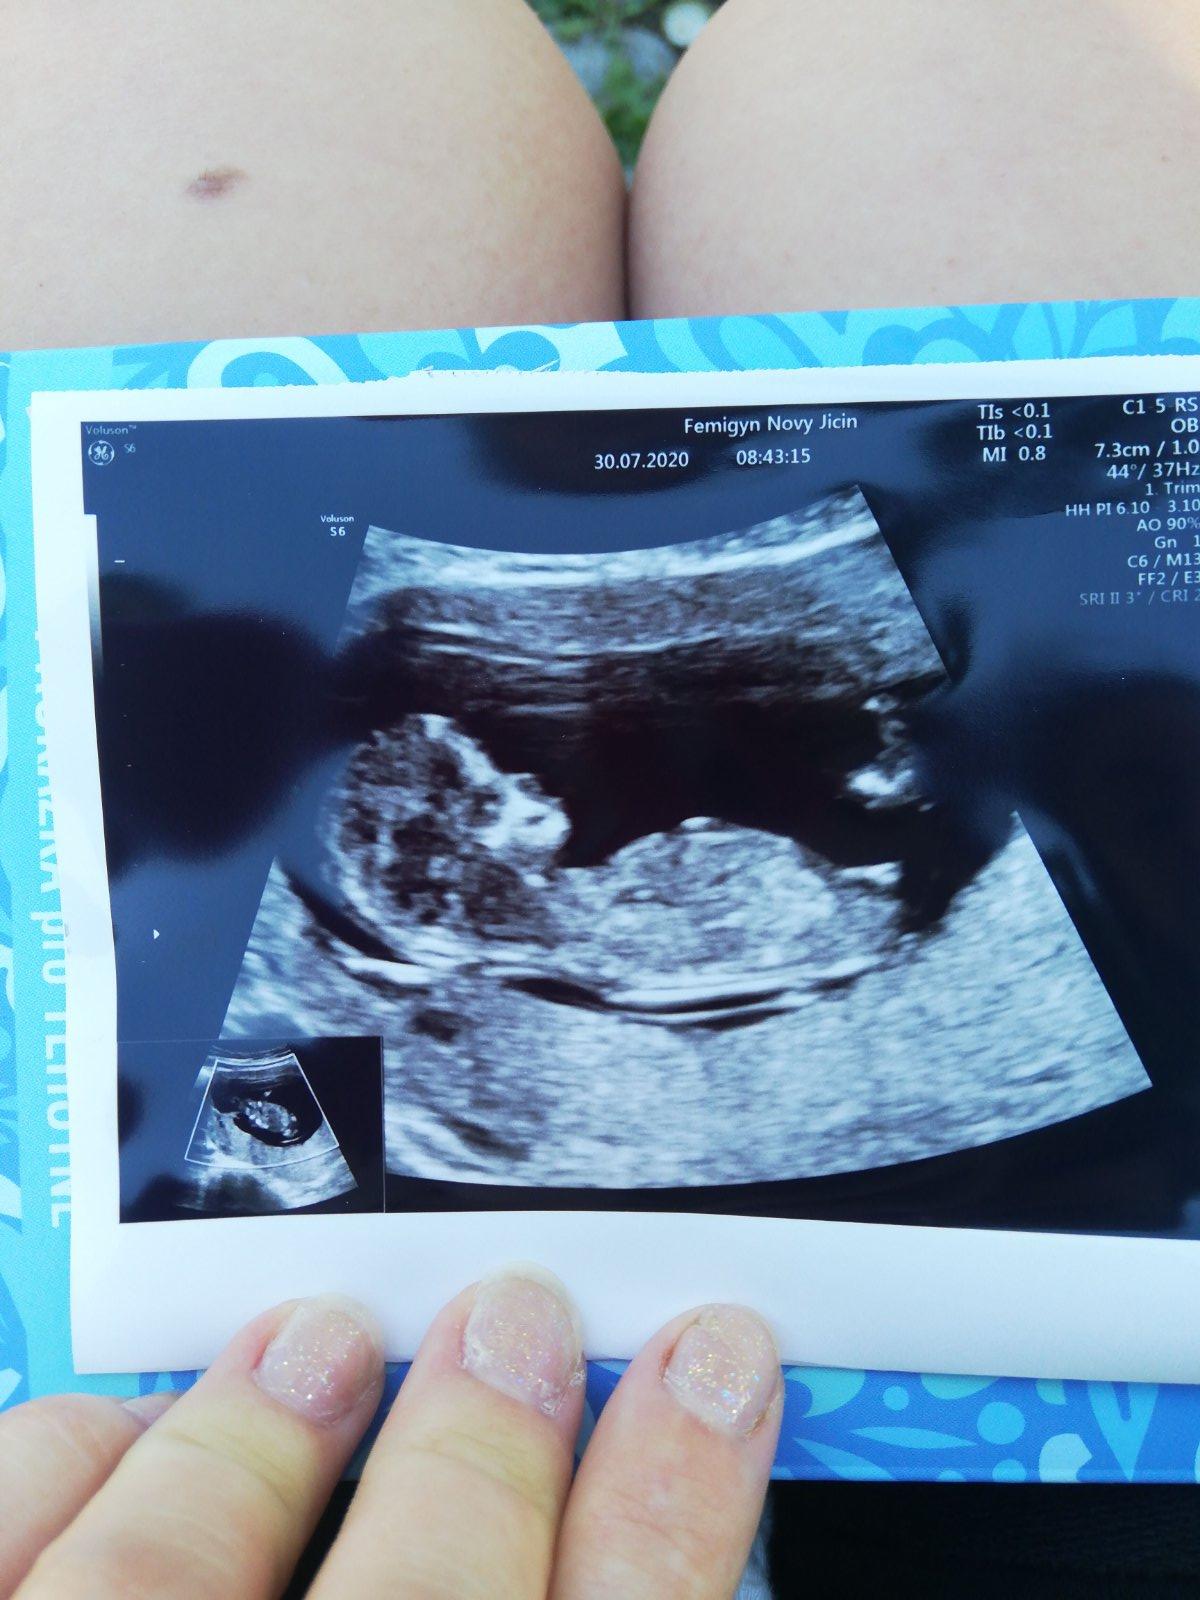

Pohlaví miminka - může to být kluk?

Ahoj holky, čekáme s přítelem první miminko.... Moc se na něj těšíme. Pohlaví nám pan doktor neurčí, musí počkat na další screening ve druhém trimestru. Ale prakticky všichni z rodiny vidí na fotkách z ultrazvuku kluka, co myslíte, může to být kluk??

Právě si nejsem jistá... vidím tam toho víc :D Máme už dva kluky a třetí už ani nebylo v plánu, ale řekli jsme si, že možná osud... uvidíme... Hlavně ať je to zdravé. 🙂